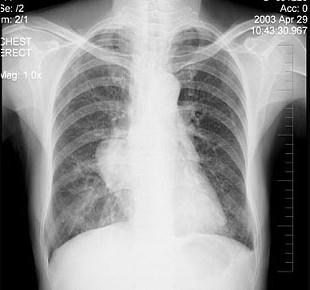

问题 女性,57岁,因胸痛,咳嗽1个月就诊,不发热,咳白色痰,无痰中带血,X线检查见图,最可能的诊断是 ( )

选项 A.右侧肺不张 B.右肺炎症 C.纵隔肿瘤 D.右肺肿瘤 E.间质性肺疾病

答案 D